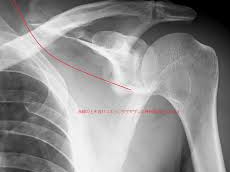

어깨에 골절이 발생하면 일상 전체가 마비되는 기분을 느끼는 것도 무리는 아닙니다. 특히 쇄골, 상완골 근위부, 견갑골 부위에 골절이 생기면 수술이 필요하며, 수술 이후의 재활과 물리치료는 단순히 통증을 없애는 것을 넘어, 관절 가동 범위의 회복과 장기적인 기능 정상화를 위한 핵심 단계입니다. 또한 어깨 골절 수술 이후 본격적으로 시작되는 재활 치료와 도수치료의 현실적인 문제는 ‘비용’과 ‘보험 적용 여부’입니다.